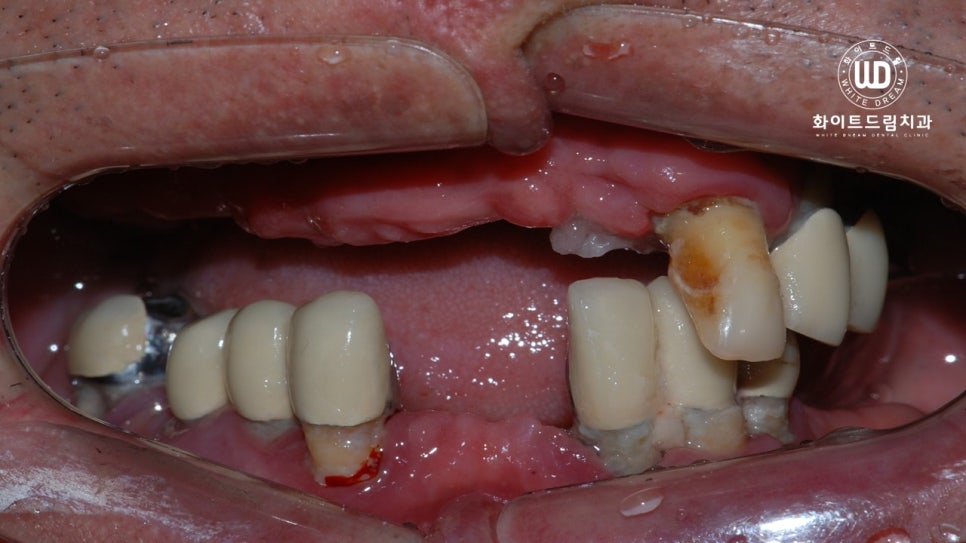

이번에 저희 치과에 내원해주신 환자분께서는 기존에 진료를 받아 부분틀니를 사용하고 계셨으며. 남아있는 치아 마저 전부 흔들려 불편함이 지속된다고 말씀해주셨는데요. 앞서 설명해 드린 대로 잇몸과 치아 사이에 염증과 출혈이 심하여 제 기능을 하지 못하는 상태이셨습니다.

사진상으로 보시면 부분틀니를 오랫동안 사용하시면서 골 소실이 많고, 잇몸과 잇몸 뼈 주변까지 염증이 진행된 상태셨습니다. 전반적으로 구강 내 염증 정도가 심했고, 오랜시간 치아가 소실되어 있어 잇몸뼈 또한 녹아내린 상태였습니다.

이전의 케이스와 비슷하게 기존 보철물들은 제거가 필요한 상태였는데요. 환자분 동의 하에 남은 치아 전체 발치 후 상악 양측 구치부 상악동 거상술 및 뼈이식 진행 후 임플란트를 식립하는 임플란트 치료과정을 적용한 사례입니다.